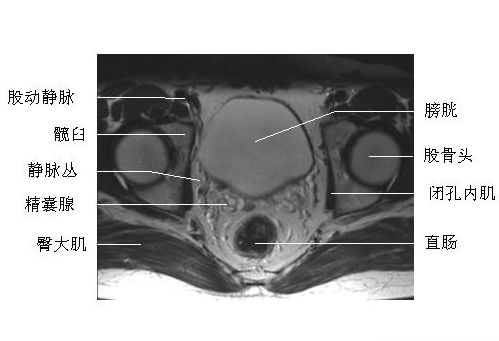

男性盆腔横断面-MRI图

男性盆腔横断面-MRI